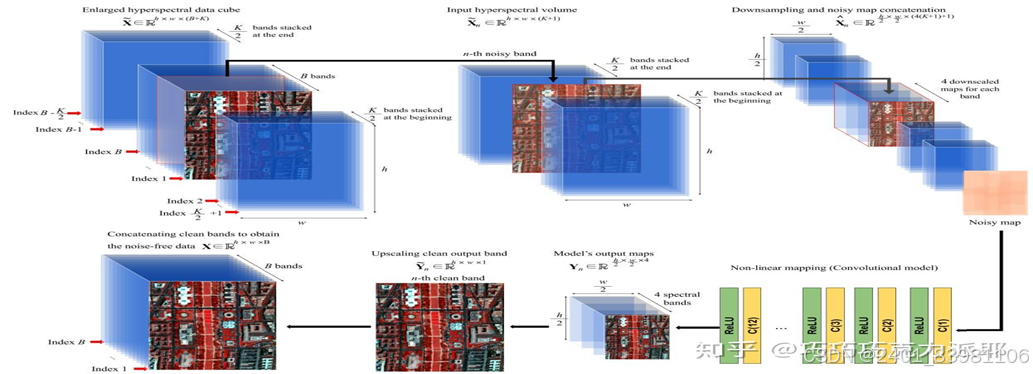

**图像预处理**:如图高光谱图像去噪(SDeCNN算法)

Li et al. 108 提出利用高光谱舌头捕捉舌头图像,然后利用隐马尔可夫模型将舌裂分为12类,该方法在舌头分类方面表现出良好的效果

进行光补偿、色彩校正、 几何变换等光补偿在图像处理中应用广泛,常见的光补偿方法有Gray World色彩均衡算法和基于白色参考图像的算法:Yu et al. 47 提出了一种在没有白色参考图像的情况下消除光不平衡的方法,即通过分割图像,估计不同背景图像的光差,然后进行光补偿来获得背景。该方法可用于分割显微医学图像以及其他医学图像。相机采集的舌头图像由于照明不均匀而产生噪点,严重影响图像质量。 48 这可以通过阈值化、扩大对比度、降低灰度值和滤除噪声等方式在低级图像处理、图像的点处理、图像的中值滤波等方面来完成。该方法可以减少预处理过程中产生的偏差,同时提高图像处理速度色彩校正主要包括环境光照条件校正、色彩空间校正、色卡色彩校正和算法校正